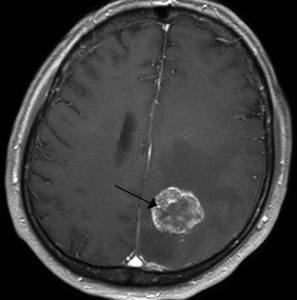

Злокачественная опухоль

Описание

Злокачественная опухоль представляет собой патологическое новообразование, состоящее из раковых клеток, способных к быстрому росту и метастазированию, что угрожает жизни человека.

Тип боли

Интенсивность и характер болевого синдрома зависят от локализации опухоли, стадии заболевания и индивидуальных особенностей пациента.

Другие проявления

На ранних стадиях опухоль может не проявляться, пока не начнет интенсивно расти. В этот момент состояние пациента ухудшается, могут возникать тошнота, утомляемость, рвота, нарушения слуха и зрения, трудности в распознавании речи, а также расстройства общей и мелкой моторики.

Клиническая картина рака разнообразна и многогранна.

Методы диагностики и терапии

Диагностика включает комплексное обследование: КТ, МРТ, рентген, лабораторные анализы, гистологию и цитологию. Лечение обычно хирургическое, с возможным назначением курса химиотерапии или лучевой терапии, а также длительного медикаментозного поддерживающего лечения.